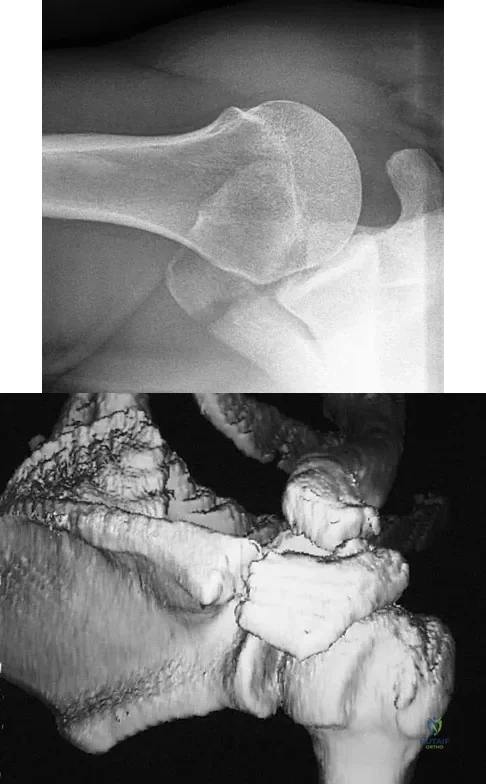

A 22-year-old right hand-dominant man who fell off his motorcycle onto the tip of his right shoulder 2 weeks ago now reports pain and difficulty raising his right arm. Examination reveals tenderness and gross movement over the lateral scapular spine and severe weakness during resisted abduction. A radiograph and 3D-CT scan are shown in Figures 24a and 24b. What is the next most appropriate step in management?

Explanation